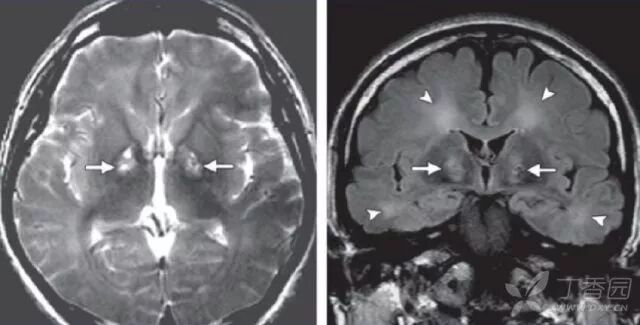

4. 影像学特点有哪些?

主要累及基底节区、丘脑、脑干及大脑皮层,累及基底节区、丘脑及脑干的病变往往表现为对称性的,累及大脑皮层的病灶往往不对称。且单纯疱疹性脑炎主要累及颞叶、额叶底部、岛叶及边缘系统。